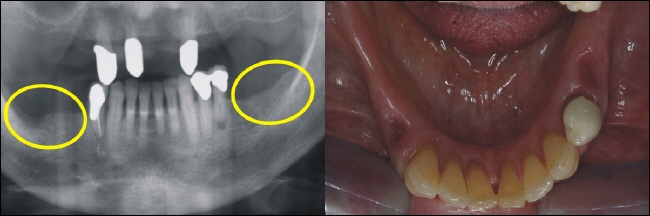

Die Ausgangssituation zeigt eine beidseitige Freiendsituation (gelbe Kreise), die bislang mit einer herausnehmbaren Klammerprothese versorgt war. Die Patientin fühlte sich in ihrer Lebensqualität stark beeinträchtigt und wünschte einen festen Zahnersatz. Das Bild rechts zeigt in der Aufsicht die zahnlosen Kieferkammabschnitte. |